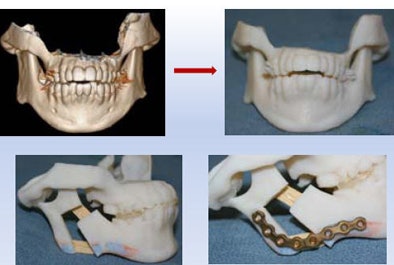

| Above, girl with severe mandibular hypoplasia (top row, preprocedure; bottom row, postprocedure) benefited from the surgeon's ability to work with a precise model (below). |

The surgeon was able to cut the mandible model and precisely fashion the prostheses, e.g., the plate that was attached, leading to a good outcome that was functionally as well as aesthetically optimal, Sosna said.